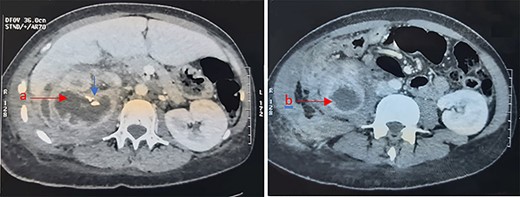

An abdominal computed tomography (CT) scan revealed an obstructive right staghorn calculus measuring 27 mm with homolateral hydronephrosis and infiltration of perirenal fat. Renal and para renal multilocular collections were described: one pararenal collection measuring 50 mm, a second collection was located in the right paracolic gutter and measuring 23 × 20 mm. An exophytic multilocular renal collection was also described, with calcifications and well-defined wall measuring 67 mm (Fig. 1).

The radiologists concluded to a xanthogranulomatous pyelonephritis with renal abscess.

Abdominal CT showing a right renal multilocular collection, measuring 67 mm (a) with calcifications (Blue arrow) and a right para renal collection measuring 50 mm (b).